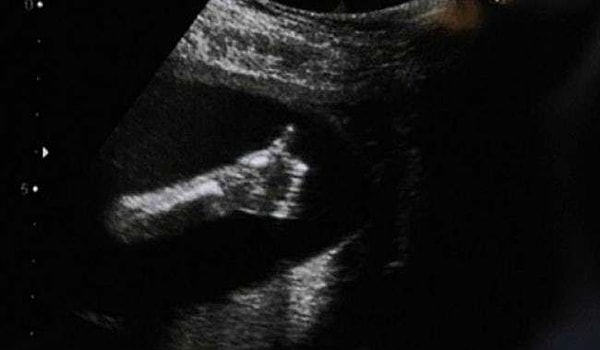

10. "Привет, мам!"